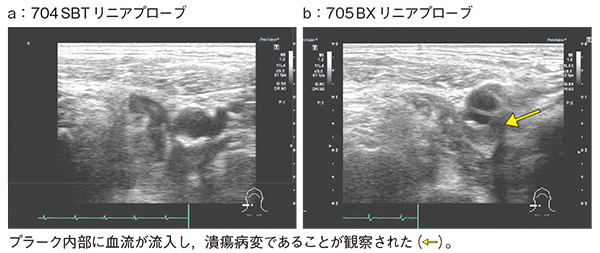

症例1は,60歳代,男性。繰り返す左片麻痺で受診。脳梗塞と診断され,精査のため頸動脈エコーを行った。従来のリニアプローブでは,高輝度のプラークが認められるものの動きはないが(図2a),PLI-705BXでは,プラーク内部に血流が流入して渦を巻いているのが観察でき(図2b),脳梗塞の原因は潰瘍病変であると判断できた。

図2 症例1:脳梗塞精査にてPLI-705BXで病変が明瞭になった症例